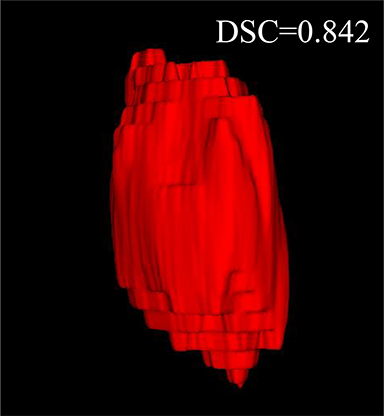

Comparison with ground truth. Some predicted results of MMFNet are shown in 2D images and 3D images in Figure 7 and Figure 8. As shown in these figures, although the shape and size of NPC are varied from each other, MMFNet can still accurately determine the regions of NPC and obtain the accurate contours of tumors. Through analyzing 2D images in figure 7, MMFNet has a capacity to fuse multi-modality MRI to reduce the confusion brought by intensity’ similarity between nearby tissues and NPC. The values of , and of MMFNet are shown in Table 1. MMFNet can reach the best results with , and .

Comparison with related works. Table 1 reports the values of , and for different methods. Predicted masks of different methods are illustrated in Figure 9 and Figure 10, which respectively present results in 2D and 3D images. Through comprehensively analyzing these results, the proposed MMFNet actually have the following properties:

(i) It directly fuses 3D MRI images rather than 2D slices. Thus, it can effectively use meaningful information from neighboring slices of MRI to realize NPC segmentation. As shown in Table 2, MMFNet can bring , and improvements in and compared to the best method based on 2D images (Multi-modality patch-based CNN). And Figure 10 shows that 3D-based methods have less isolated regions (false positives) than 2D-based ones.

(ii) It segments NPC by fusing multi-modality MRIs with the multi-encoder network. Thus, it can learn complementary and interdependent features from different modalities of MRI for final decisions. Additionally, comparing with input-level fusion networks and decision-level fusion networks, layer-level fusion networks (including MMFNet) can effectively capture informative features from different modalities of MRI and fuse low-level features and high-level features.

(iii) It uses a fusion block to fuse low-level features from different modalities of MRI and prepare these low-level features for the fusion with high-level features. Thus, it can more effectively fuse information from various sources. It also uses the self-transfer strategy to initialize the netwerk. Hereby, it can stimulate encoders to make full mining of meaningful features from modality-specific MRI. And it finally improve base multi-encoder-based network (Merging encoders’ fetures) by , and in and .